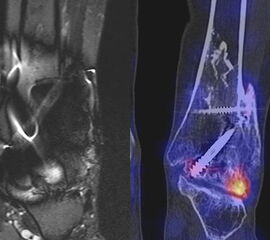

Beispiele für SPECT/CT-Untersuchungen nach OSG-TEP sind in den Abbildungen 6.1. bis 6.3. abgebildet.

Gurbani et al. evaluierten 37 Patienten mit schmerzhaften Sprunggelenkprothesen mit SPECT/CT und korrelierten die Ergebnisse mit klinischen und intraoperativen Befunden. Die SPECT/CT-Ergebnisse korrelierten zu 89,2 % (33/37 Pat.) mit der definitiven Diagnose. 28 Patienten wurden operativ revidiert und der Vergleich der SPECT/CT-Befunde mit den intraoperativen ergab eine Übereinstimmung von 92,9 % (26/28 Pat.). Die SPECT/CT identifizierte in den meisten Fällen aseptische Lockerungen (12/33 Pat.) und Impingement (11/33 Pat.). Seltenere Diagnosen waren Fehlstellungen (4/33 Pat.), Zystenbildungen (2/33 Pat.), subtalare Arthrosen (2/33 Pat.) und Infektionen (2/33 Pat.) 51.

Die Autoren beschreiben einen Fall, der neben einem Fokus am lateralen Malleolus auch eine starke flächige Anreicherung am talaren Prothesen-Knochen-Interface 17 Monate nach TEP-Implantation aufwies, so dass neben dem Verdacht auf ein laterales Impingement auch der Verdacht auf eine Lockerung der talaren Prothesenkomponente geäußert wurde. Intraoperativ bestätigte sich die Lockerung der talaren Prothesenkomponente nicht, sondern nur das laterale Impingement, welches mittels Debridement erfolgreich therapiert wurde 51. Da der Pat. bereits vor der TEP-Implantation eine Triple-Arthrodese erhalten hatte (welche im SPECT/CT unauffällig war), kann eine solche flächige Mehrspeicherung auch als weitgehend asymptomatische Stressreaktion gewertet werden.

Mertens et al. 52 berichten unter Anwendung eines standardisierten Auswerte-Schemas über eine Treffsicherheit von 96 % (Sensitivität 100 %, Spezifität 80 %) des SPECT/CT zur Diagnose der Ursachen für eine schmerzhafte Sprunggelenkprothese (n=24). Der SPECT/CT-Befund führte in 86 % zu einer spezifischen Therapie, welche in 83 % der Fälle zum Therapieerfolg führte.